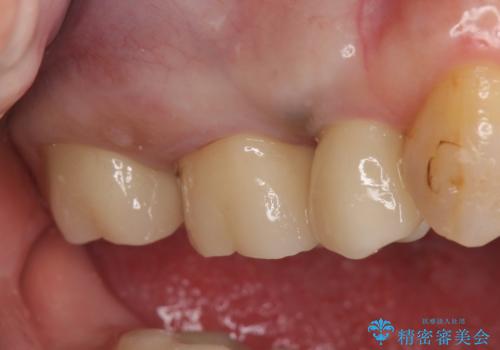

- 右上の奥歯がしみるので診て欲しいといらっしゃった方の症例です。

診査の結果痛みの原因は右上7番目だったため、古い樹脂と虫歯を除去後、オールセラミッククラウンによる補綴を行いました。

また右上5、6番目の歯も治療を希望されたため、オールセラミッククラウンによる補綴を行いました。